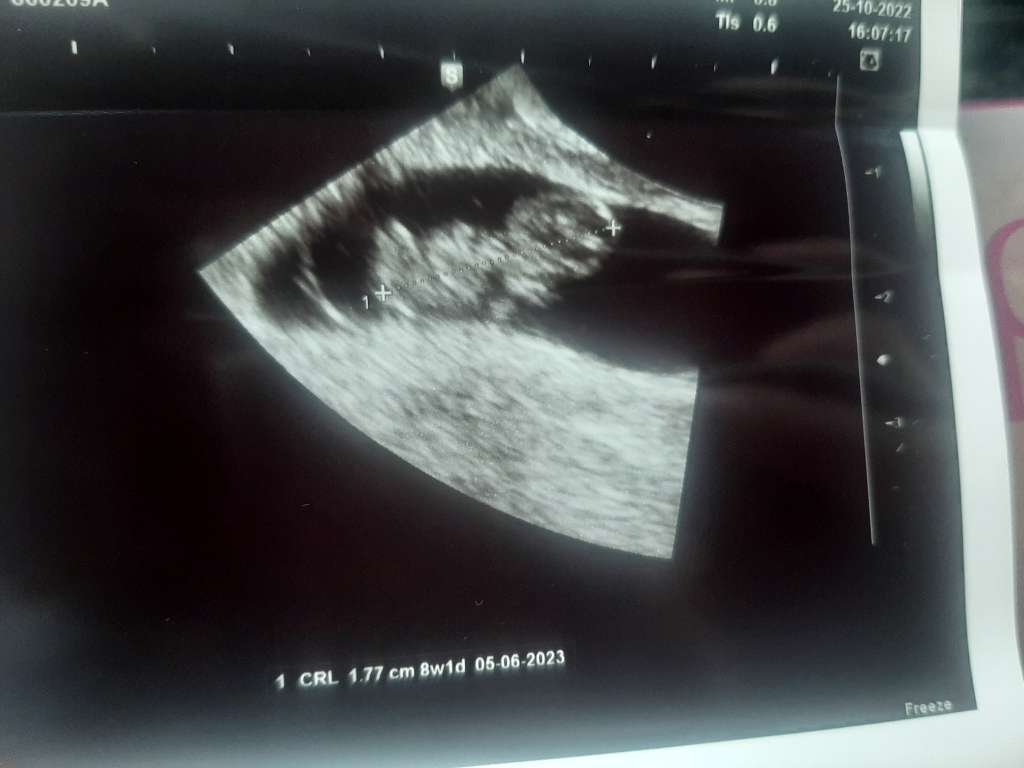

hej hej 😃 Jestem! Serduszko pięknie bije, termin z om 31.05 z USG 05.06 i tego drugiego się trzymamy. Trzymam kciuki za całą reszte ❤️

Dziewczyny ja już po 🥰 Wszystko prawidłowo, widziałam serduszko ❤️❤️ Wg OM 7+3, według dzisiejszego USG ciąża młodsza 6+3, termin porodu 17.06. ☀️ Dostałam skierowania na badania, kolejna wizyta 29.11. i wtedy będę miała założoną kartę ciąży ☺️

mamy ten sam termin OM i u mnie tez ciaza młodsza 😊. 3 dni różnicy, bo ja mam dzisiaj 6+6, ale z każda wizyta ten termin może być inny 🙈